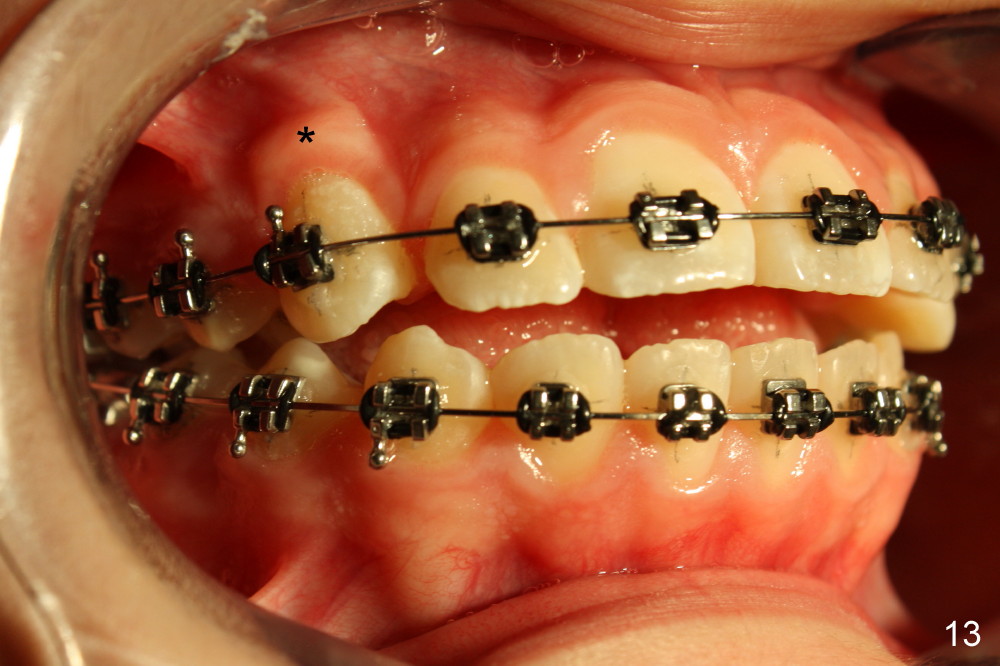

One month later, the canines has erupted completely at the expense of aggravation of anterior open bite (Fig.13,14, compare to Fig.11,12). Elastics are placed between the upper and lower incisors (Fig.14) following placement of .016' stainless steel wire for the upper arch (Fig.13).